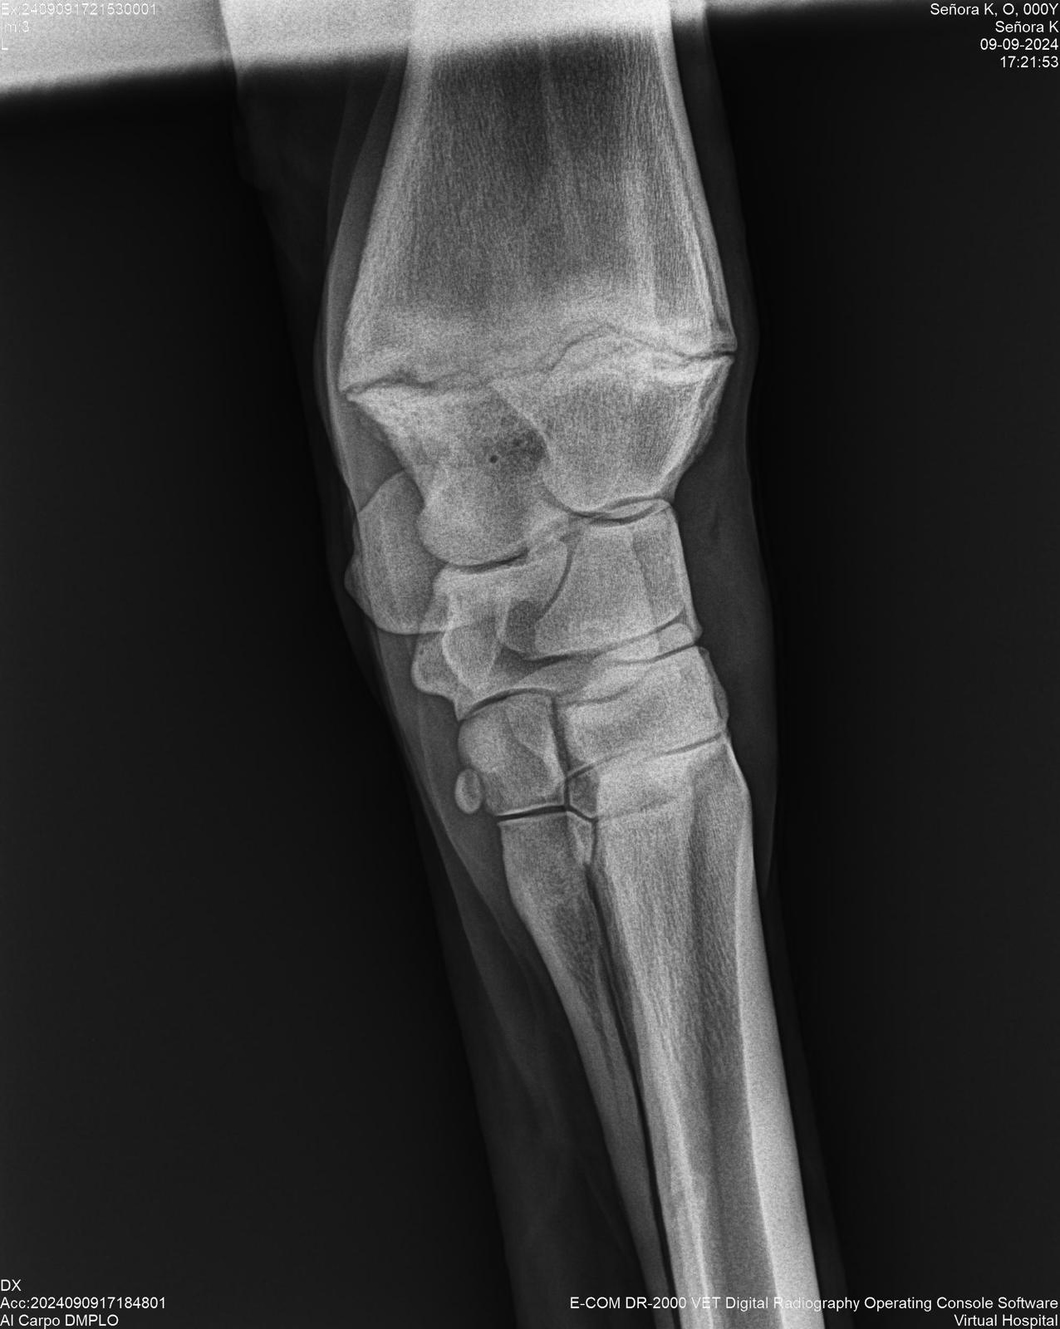

LOTE 44, SEÑORA K

Identificador: #291147-

Generacion 2022